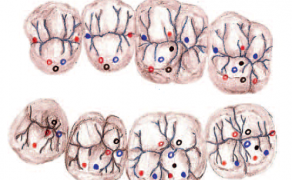

STRESZCZENIE: Artykuł przedstawia etapy wykonania uzupełnienia protetycznego z zastosowaniem metody analogowej i cyfrowej.

SUMMARY: The article presents the stages of fabricating a prosthodontic restoration using an analogue and a digital method.

Czasami musimy się decydować na niekonwencjonalne metody, łącząc różne rozwiązania techniczne, aby sprostać ograniczeniom, jakie stawiają nam lekarz prowadzący, pacjent z jego wyobrażeniem gotowej pracy oraz przede wszystkim pole protetyczne, układ stomatognatyczny i możliwości spełnienia wszystkich oczekiwań. W tej pracy lekarz nie mógł wkręcić implantów w innych miejscach ze względu na zbyt cienką kość w miejscach zębów przedtrzonowych i zębów trzonowych. Dlatego wyszliśmy z pomysłem pracy kombinowanej przykręcanej na multiiunitach z poziomu implantów, co pozwoliło wykonać pracę, która jest funkcjonalna oraz „wygodna” – spełniająca większość oczekiwań.

Etapy pracy

- Po odlaniu wycisku, sporządzeniu planu pracy, wstępnego kosztorysu oraz uzyskaniu zgody lekarza i pacjenta przystąpiliśmy do kolejnych etapów.

- Zamówione zostały komponenty implantoprotetyczne, w tym: dwa proste i [...]